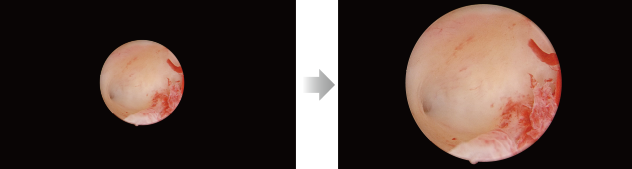

Small diameter scope scene (e.g. hysteroscope)

Intelligent Image Algorithm, Even in Extreme Circumstances

Intelligent Image Algorithm, Even in Extreme Circumstances

A variety of image post-processing algorithms make up for uneven lighting, local overexposure, thick fog etc., delivering clear, structured and layered images even in extreme scenarios.

Homogenous Brightness

Detail Enhancement

Color Enhancement

Before

After

Small diameter scope - One Touch to inscribed circle